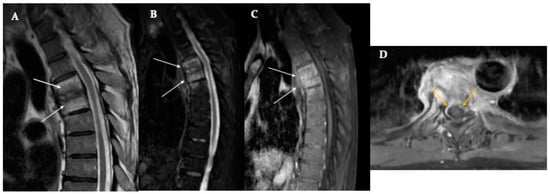

8.3. Ankylosing Spondylitis